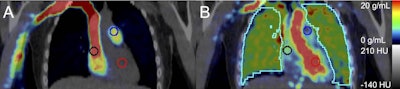

Participants underwent PET imaging with a radiotracer (F-18 NOS) that binds to a nitric oxide enzyme (iNOS) in pulmonary tissue. iNOS is a PET biomarker associated in prior studies with acute and chronic inflammatory diseases. A blood sample was also obtained to measure cytokine concentrations.

On the PET images, e-cigarette users showed greater binding activity between the tracer and iNOS than cigarette smokers (p = 0.03) and never smoked/vaped controls (p = 0.01), whereas binding in cigarette smokers did not differ from controls (p > 0.1), according to the results.

Moreover, F-18 iNOS binding in the lung imaging correlated significantly with blood concentrations of tumor necrosis factor alpha (TNF-a) (Spearman's rank correlation = 0.87, p = 0.05) in e-cigarette users. TNF-a is a potent inflammatory cytokine that responds to injured lung tissue.